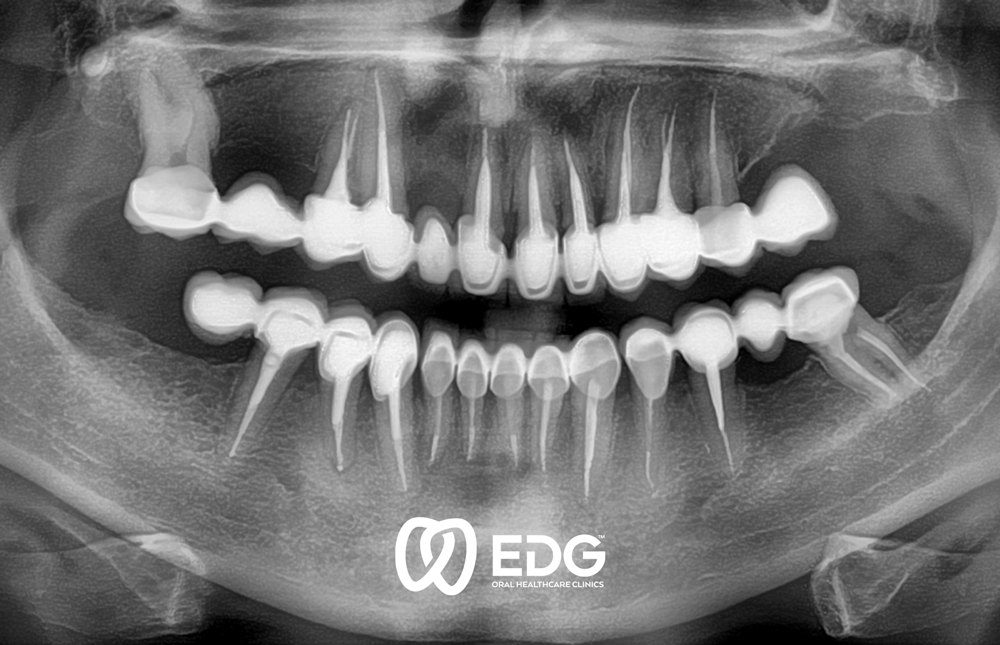

Губењето на забот може да се должи на различни причини: кариес, пародонтопатија или од повреда. Во одделот за протетика, на нашите пациенти им нудиме современа нега, со што се воведуваат естетски и функционални стандарди и индивидуални барања. Инсистираме на неразделна врска помеѓу формата и функцијата на стоматолошката протетика. Само функционално добрата работа доведува до добри естетски резултати. За избор и изработка на забна протеза, објективните критериуми играат улога, како и типот и возраста на пациентот. Комплексната протетска реконструкција на забите бара прецизна и обемна дијагностика пред да се започне со реконструктивни мерки. За да го направите ова, неопходна е темелна медицинска анамнеза, како и РТГ дијагностика и употреба на современи методи за точно утврдување на положбата на забите и движењето на зглобот на темпоромандибуларниот (виличниот) зглоб. За протетска реставрација, користиме модерна технологија за коронки и мостови, делумни и целосни протези и импланти.